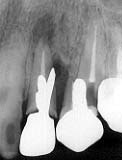

27歳 男性 「6 デンタルX線写真

初診時 パノラマ 近心の歯根および周囲骨の吸収が著明

臼歯部にカリエスが認められるものの、清掃状態は比較的良好。矯正治療により左右両側の小臼歯 は抜歯されており、第一大臼歯は全て治療済みであった。「6は、矯正治療終了後抜髄処置を受けた とのことである。「6舌側歯肉縁に破折線様の欠損が認められ、動揺も著明で時々腫脹を繰り返して いるとのことであった。

レントゲン診査の結果、「6舌側の歯根吸収と周囲歯槽骨の吸収像が認められた。特に近心側の 歯槽骨吸収は隣在歯の根尖に至る状況であったため、抜歯することとした。。

歯根吸収の原因は、矯正(力)によるものか、根管治療によるものかは不明である。咬合診査の 結果、特に異常な咬合圧が加わったような形跡はない。